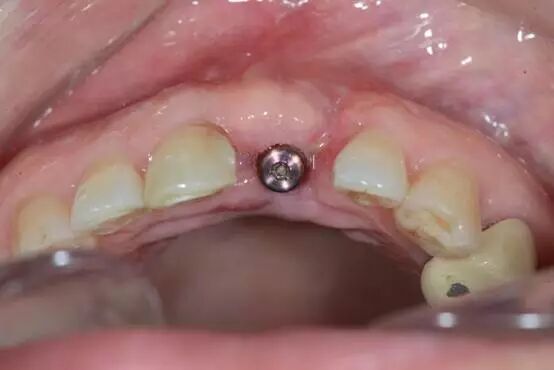

二期植入種植體

覆蓋軟組織修復(fù)膜

5.0線縫合 唇側(cè)

術(shù)后四周? 顎側(cè)

唇側(cè)